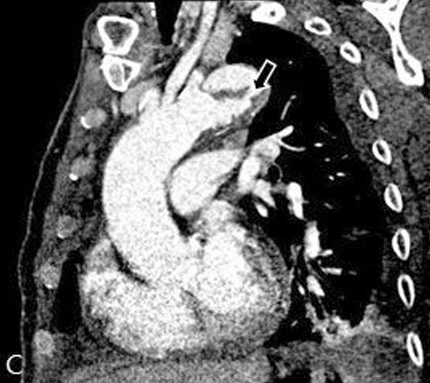

Fig 1C

Curved multiplanar image at aortic arch level (C) demonstrated the proximal intimal tear site of the dissection (black arrow).